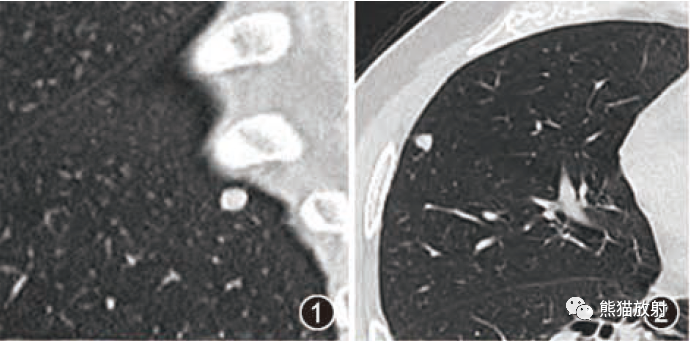

张力性纵隔气肿影像表现及严重度分级  迅速增大的肺部结节,首先考虑良性,确诊需要肺穿